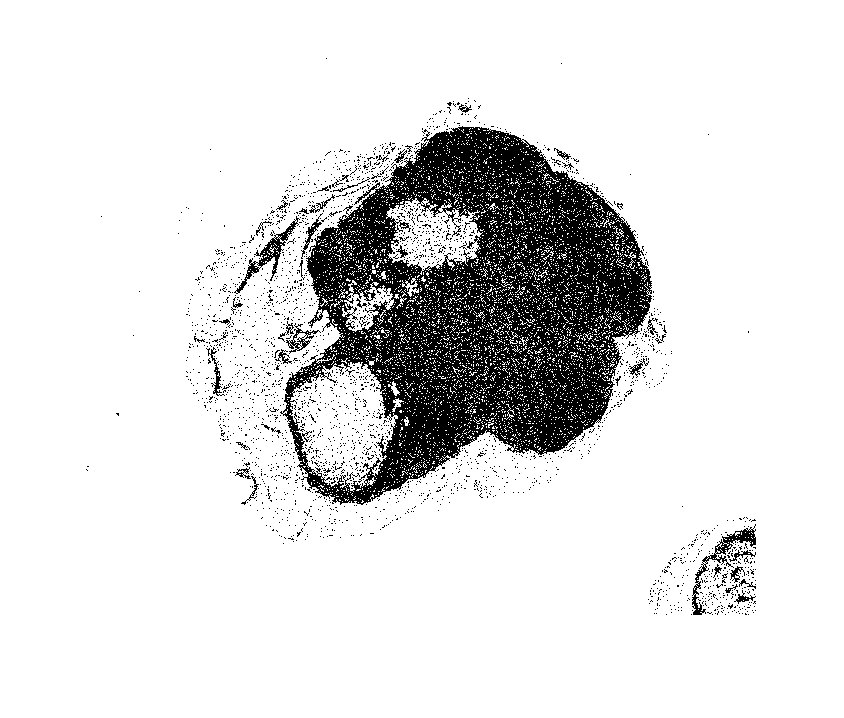

imshow(imRegion);

Моделируйте с этой областью, затем отображают результаты.

imRegionGray = rgb2gray(imRegion); thresh = graythresh(imRegionGray); imLowResQuant = ~imbinarize(imRegionGray,thresh); imshow(imLowResQuant)